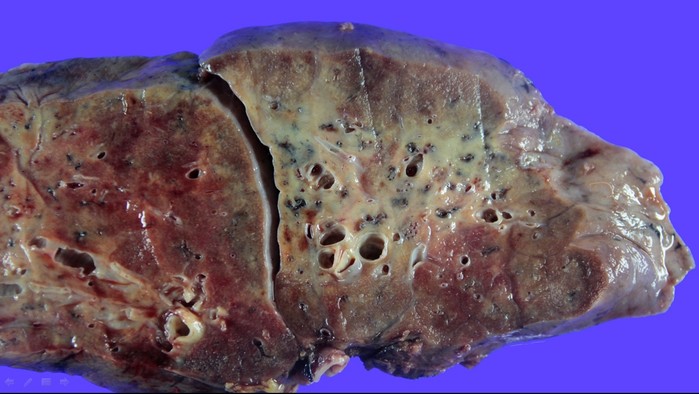

에크모센터장 흉부외과 김형수 교수는 “코로나19 환자 중 국내에서 최고의 중증치료 사례였으며 코로나바이러스에 감염된 폐를 떼어낼 때 건강한 폐와 다르게 크기도 작게 수축 되었고 마치 돌덩이처럼 폐가 딱딱한 느낌이었다”며 “건강하고 젊은 코로나19 감염증 환자도 폐섬유화 진행 속도가 빨라 폐이식까지 갈 수 있으니 젊다고 방심하지 말고 감염을 막기 위한 사회적 거리두기, 마스크 착용 등의 노력을 지속해야 한다”고 강조했다.

| ▲ 코로나19 환자 폐 단면 |